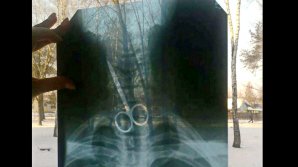

Два часа на операцию: в Институте кардиологии хирурги научились устанавливать искусственный аортальный клапан